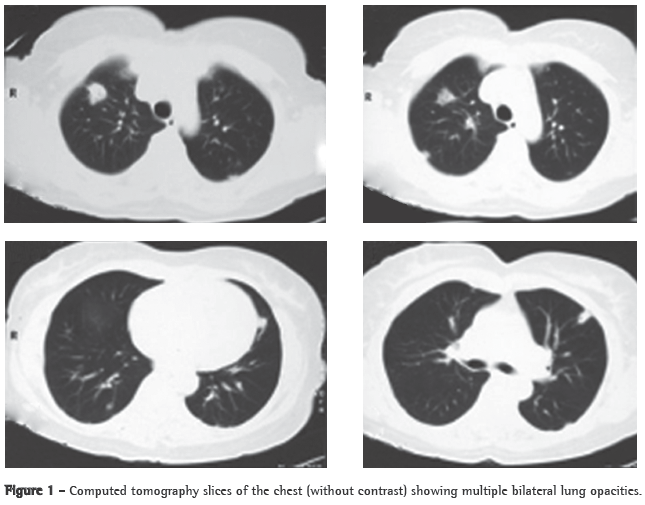

Abstract Lemierre's syndrome is characterized by acute oropharyngeal infection, complicated by internal jugular venous thrombosis secondary to septic thrombophlebitis, and by metastatic infections in various distant organs-most commonly in the lungs. We report a case of Lemierre's syndrome in a 56-year-old female who presented with right-sided neck mass and fever. Right internal jugular venous thrombosis was demonstrated on an ultrasound. A computed tomography scan of the chest revealed multiple opacities throughout both lungs. An open surgical biopsy was performed due to suspicion of pulmonary metastases. Anatomopathological examination revealed septic emboli in lung parenchyma. Retrospectively, the patient reported a history of pharyngitis two weeks prior to hospitalization. After the diagnosis had been made, the patient was treated with broad-spectrum antibiotics (cefuroxime for 7 days and azithromycin for 5 days; subsequently, because fever persisted, cefepime for 7 days). One month later, a computed tomography scan of the chest revealed resolution of the opacities.

A 56-year-old Caucasian female sought treatment in the emergency room presenting a painful, right-sided neck tumor for 5 days. The patient reported a dry cough and high fever for 3 days. She described herself as a nonsmoker. She was hypertensive and diabetic. She had experienced a myocardial infarction 3 years prior. At admission, the patient was dehydrated and afebrile (axillary temperature, 36.7°C). She presented normal respiration. Laboratory tests revealed increased erythrocyte sedimentation rate (92 mm). Ultrasound of the neck showed IJV thrombosis, and anticoagulation was started on post-admission day 4. A chest X-ray demonstrated at least two nodules in the left lung, one apparently cavitated and one with a diameter of 18 mm at its base, as well as an irregular lesion, 25 mm in diameter, in the right upper lung lobe. A transesophageal echocardiogram, performed in order to rule out endocarditis, demonstrated no vegetation. Due to the hypothesis of pneumonia, empirical treatment with oral cefuroxime (500 mg every 12 h) was started. A computed tomography scan of the chest revealed multiple bilateral lung opacities, with an aspect suggestive of metastatic implants (Figure 1). The patient was then submitted to fiberoptic bronchoscopy, the findings of which were normal. In the microbiological analysis of the bronchoalveolar lavage fluid, testing for acid-fast bacilli and fungi were negative, as were the cytopathologic study and cultures. Since the working diagnosis was metastatic neoplasm, the patient underwent surgical lung biopsy. The anatomopathological examination of the sample showed chronic suppurative inflammation with organizing abscesses in lung parenchyma. In view of the hypothesis of Lemierre's syndrome caused by jugular thrombosis accompanied by septic pulmonary embolism, the patient was questioned regarding the occurrence of tonsillitis at the onset of the disease. The patient had no recollection, but her daughter remembered that the patient had used oral amoxicillin (500 mg every 8 h for 10 days) for the treatment of tonsillitis some days prior to hospitalization. At hospital admission, the patient received a course of intravenous cefuroxime (750 mg every 8 h for 7 days) concomitantly with oral azithromycin (500 mg once a day for 5 days). Subsequently, because fever persisted, she was treated with cefepime (1,000 mg every 12 h for 7 days). A control computed tomography scan of the chest performed after this course of antibiotics showed nearly complete resolution of the opacities (Figure 2). The patient had been afebrile since the third day of the new course of antibiotics. No microorganisms were isolated from blood cultures or bronchoalveolar lavage cultures. Since there is no evidence that it is beneficial in cases of Lemierre's syndrome, anticoagulation was discontinued after 20 days.